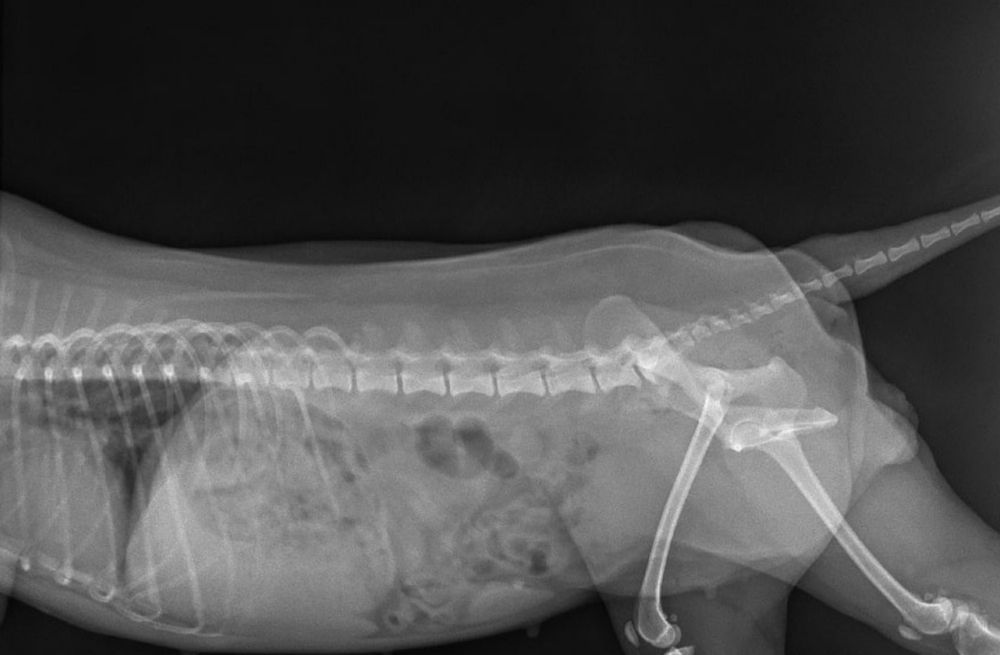

También contamos con radiografía veterinaria con rayos X, una herramienta fundamental para diagnosticar fracturas, lesiones articulares, problemas respiratorios o alteraciones internas. Si buscas un veterinario con rayos X en Torrejón, en nuestra clínica realizamos estudios radiológicos rápidos y seguros.